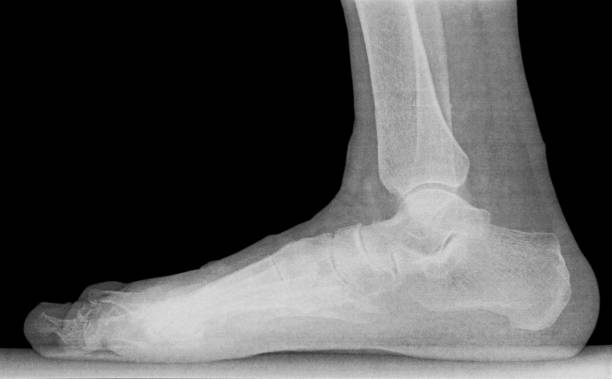

발뒤꿈치가 아픈 이유 다섯 번재는 발목 터널 증후군입니다. 내측 복사뼈와 발뒤꿈치 뼈 사이의 족근관을 관통하는 후경골 신경이 눌리거나 손상되면 저림, 작열감 등을 느끼게 됩니다. 이때는 신경 압박에 의한 통증이기 때문에 앞서 언급한 연조직 손상과 달리 통증의 위치가 명확하지 않고 신경 경로를 따라 퍼지는 특성을 갖고 있습니다.